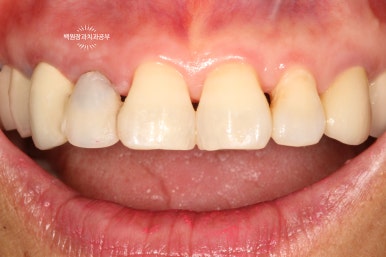

오른쪽 위 가쪽 앞니 (측절치)가 뿌리만 남아있는 것을 보실 수 있을겁니다. (잔존 치근)

대부분.. 아니 거의 100이면 100 일반 치과에서 발치 즉시 임플란트를 권하게 됩니다.

왼쪽: 오른쪽 위 측절치의 이차우식으로 인한 파절, 오른쪽: 외과적 정출술 2년 뒤

어쨌든 보시면, 왼쪽은 외과적 정출술 (surgical extrusion) 이전의 모습이고 오른쪽은 치료 2년 뒤 모습입니다.